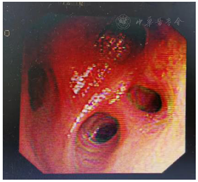

分别于2020年8月5日、2020年9月5日行卡瑞利珠单抗免疫治疗+吉西他滨(1.2 g d1)+顺铂(100 mg d1)方案化疗两周期,期间出现II度骨髓抑制,予以对症处理后好转,均未行第8天吉西他滨治疗。2020年9月行气管镜检查提示右上叶管腔内新生物消失,管腔通畅,粘膜光滑,胸部CT提示右肺下叶支气管扩张,未见新发肺部病变,疗效评价为完全缓解。故于2020年9月28日、2020年11月12日、2020年12月9日再次行卡瑞丽珠单抗联合化疗3周期,具体用药方案同前,期间患者反复出现II度骨髓抑制,予以相关处理。肝肾功能、肿瘤指标及胸部CT稳定,未见明显消化道反应及其他毒副反应。